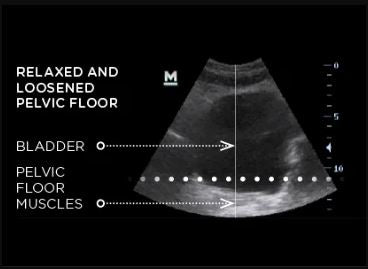

Key effectiveness is based on focused electromagnetic energy. A single EMSELLA session induces thousands of supramaximal pelvic floor muscle contractions, which are extremely important in muscle re-education of incontinent patients.